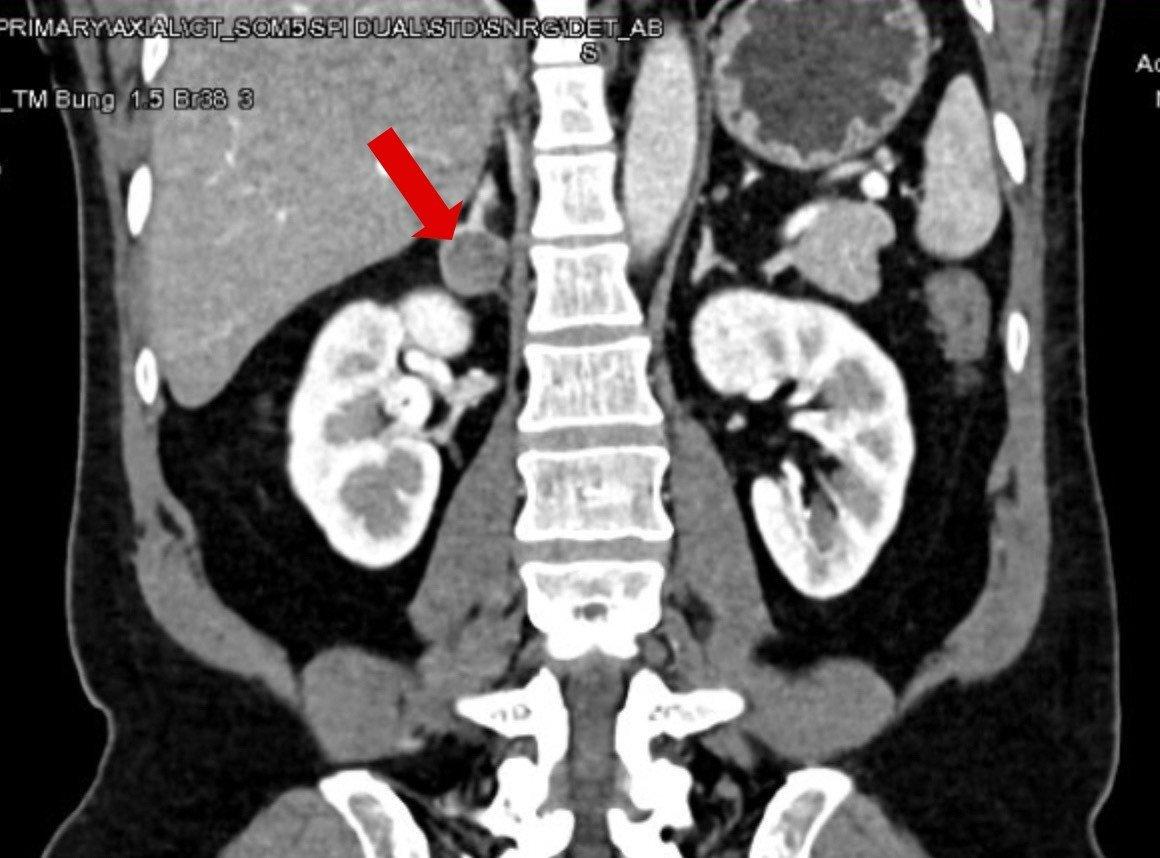

Kết quả cho thấy, bệnh nhân có một khối u nhỏ với kích thước 25 mm ở tuyến thượng thận phải. Vì là khối u rất nhỏ nên rất khó phát hiện, nhưng đây chính là nguyên nhân khiến người bệnh tăng huyết áp bất kiểm soát và chứng hạ kali suốt thời gian qua, bác sĩ Duy nhận định.

Khối u ở tuyến thượng thận phải gây ra tình trạng huyết áp tăng cao, khó thở kéo dài ở người bệnh. Ảnh: BVĐK Tâm Anh cung cấp

Ngay sau đó một cuộc hội chẩn liên khoa diễn ra giữa các bác sĩ Khoa Nội tiết và Trung tâm Tiết niệu Thận học, các bác sĩ thống nhất phương án phẫu thuật cắt tuyến thượng thận phải cùng khối u bằng phương pháp nội soi 3D. “Khối u có kích thước tuy nhỏ nhưng lại gây ra hệ lụy lớn đến sức khỏe cho người bệnh”, bác sĩ Nguyễn Hoàng Đức, người trực tiếp phẫu thuật cho người bệnh, nhận định.